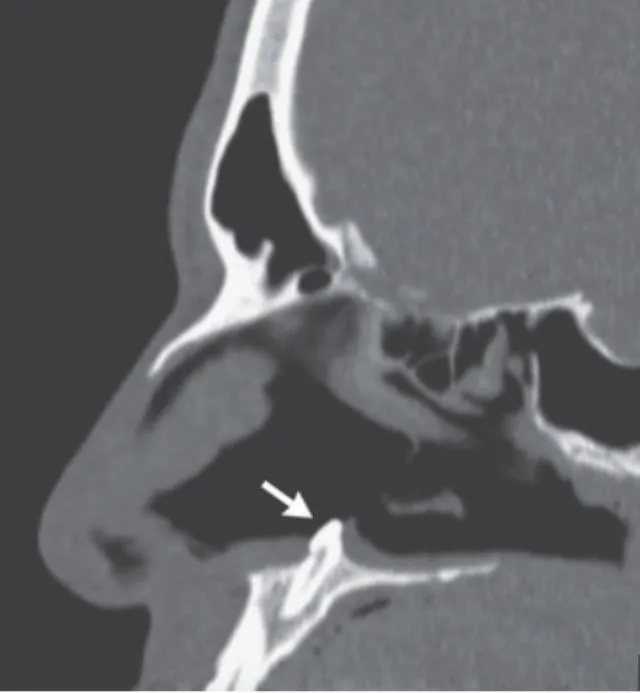

Çünkü adamın burnundaki tıkanıklığa neden olan şey, orada olmaması gereken dişti.

Dergideki yazıda, “Hasta bir kaç yıldan bu yana burun tıkanıklığı yaşadığını belirtti ancak daha önce yüz travması ya da başka bir anormallikle karşılaşmadığını anlattı. İlk muayenenin ardından buruna takılan kamera sayesinde, burunda olmaması gereken bir diş parçası tespit edildi. Bu parça başarılı ameliyat sonucu alındı” ifadelerine yer verildi.